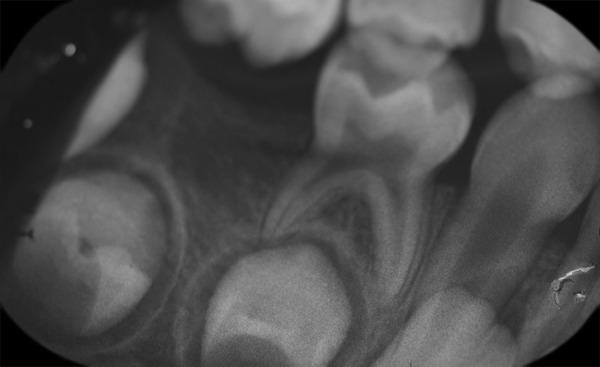

Hidden caries is a dentinal lesion beneath the dentinoenamel junction, visible on radiographs. A single report described this lesion in primary dentition. This case report describes a case of hidden caries in a mandibular second primary molar, misdiagnosed as malignant swelling. A 3-year-old white girl was referred to the Department of Pediatric Dentistry with a chief complaint of pain and extraoral swelling on the right side of the mandible for the last 3 months. She was earlier referred to the surgical department for biopsy of the lesion. Radiographic and computed tomography scan examination showed a periapical lesion with buccal plate resorption and radiolucency beneath the enamel on the mesial part of tooth 85. The tooth was extracted, and follow-up of 2 years showed normal development of tooth 45. The main problem is early detection and treatment, since the outer surface of enamel may appear intact on tactile examination.

隐匿性龋是位于牙本质釉质界下方的牙本质病变,在X线片上可见。有一份报告描述了乳牙列中的这种病变。本病例报告描述了一例下颌第二乳磨牙隐匿性龋被误诊为恶性肿胀的病例。一名3岁白人女孩因右侧下颌疼痛和口外肿胀3个月为主诉被转诊至儿童牙科。她之前被转诊至外科进行病变活检。X线片和计算机断层扫描检查显示85号牙近中部分根尖周病变伴颊侧板吸收以及釉质下方的透射区。该牙被拔除,2年的随访显示45号牙发育正常。主要问题是早期发现和治疗,因为在触诊检查时釉质外表面可能看起来完好无损。